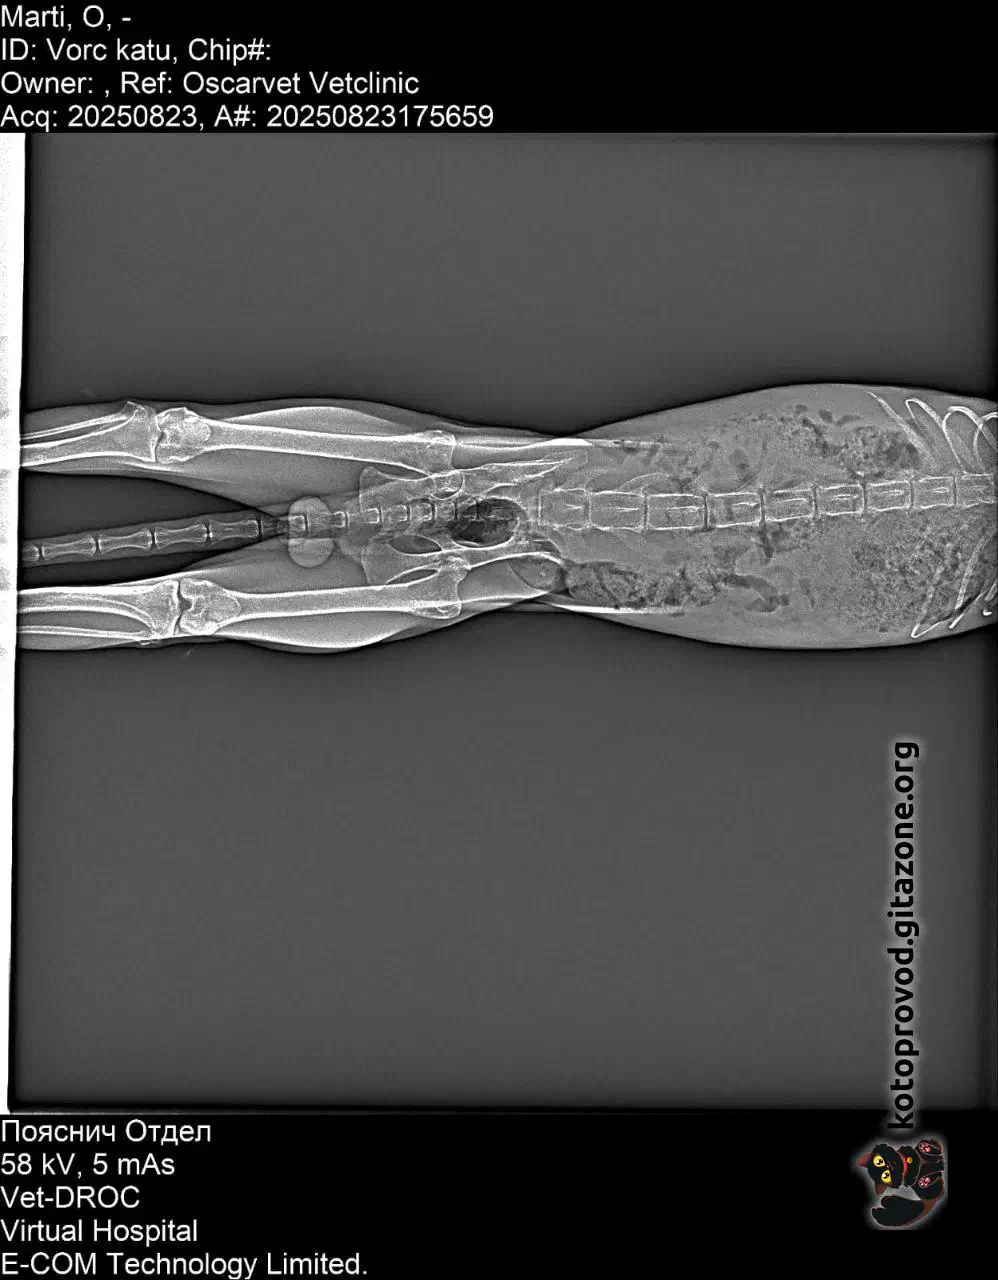

Martini (white-and-ginger) is a boy, his age is still unclear. Blood tests and an ultrasound were done, but there’s still no clarity about the diagnosis. There are several hypotheses, each worse than the other. Facts: the pancreas, kidneys, and liver are deformed, their structures are impaired. Blood results suggest possible problems with blood formation. The least of his troubles is an old pelvic injury that makes it difficult for him to move. He is likely in pain.

X-Ray images